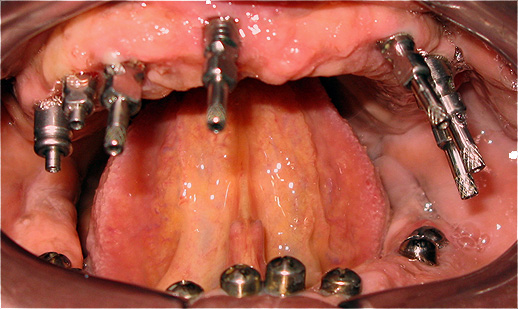

Caso 3 - Desdentado total reabilitado com prótese acrílica removível inferior, barra e clips para retenção e estabilidade

![]() |

![]() ![]() |